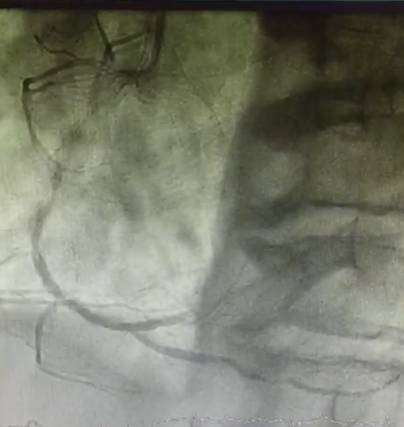

Angiogram